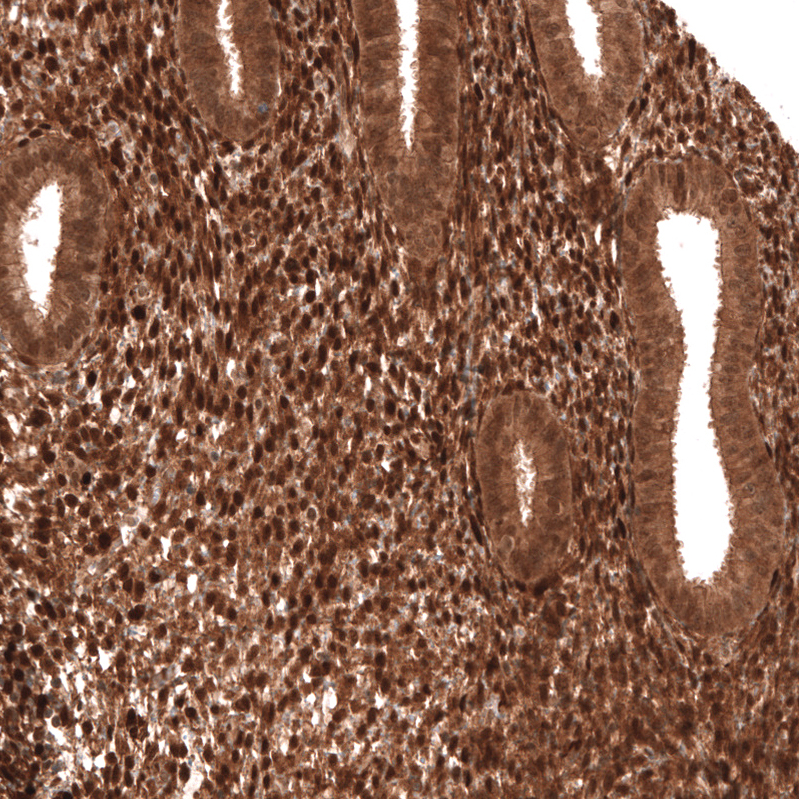

Immunohistochemistry analysis in human lymph node and skeletal muscle tissues using AMAb91735 antibody. Corresponding PTEN RNA-seq data are presented for the same tissues.